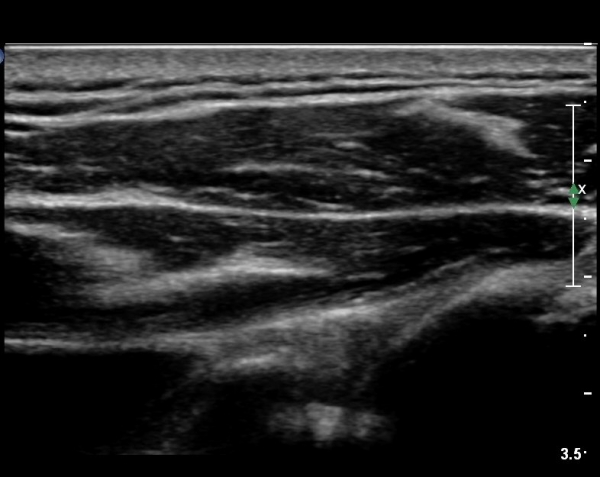

ÃÊÀ½ÆÄÀ¯µµÇÏ ÈíÀÎÄ¡·á ÈÄ ´ëºÎºÐÀÇ ¼ö¾×ÀÌ Á¦°Å µÈ °ÍÀÌ È®ÀεȴÙ(»çÁø 8).

º» Áõ·Ê¿¡¼­´Â 22G¹Ù´Ã·Î ÈíÀÎÀÌ ¾ÈµÇ¾î 18G ¹Ù´Ã·Î ¾à 5cc ¼ö¾×À» ÈíÀÎÇÏ¿´À¸¸ç

ÈíÀÎ ÈÄ Áï ½Ã Áõ»çÀÇ È£Àü°ú  ¼öµ¿Àû ³»Àü ½Ã ÅëÁõÀÌ ¼Ò½ÇµÇ¾ú´Ù.